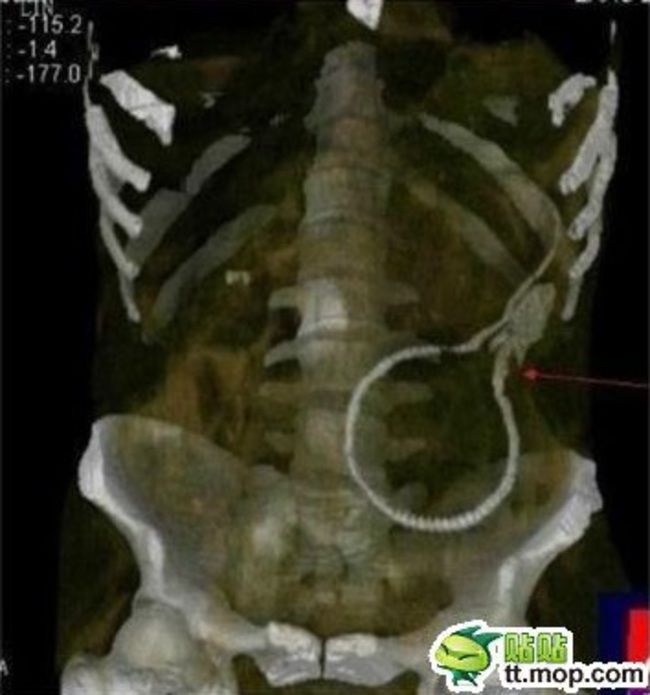

肛門にウナギを入れた男のレントゲン写真が流出

gif_animation 中国での珍事件。おそらくは ”性的な欲求” のために自分の肛門にウナギを入れた男。女医がネット上に公開したというレントゲン写真。[4]images